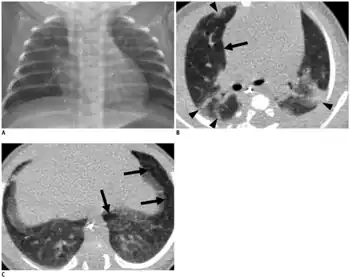

| An X-ray showing bronchopulmonary dysplasia. Person is also intubated and has an oral gastric tube. | |

- CXR shows with hyperinflation, low diaphragm, atelectasis, cystic changes.

- Chest radiograph with diffuse abnormal findings characteristic of BPD.